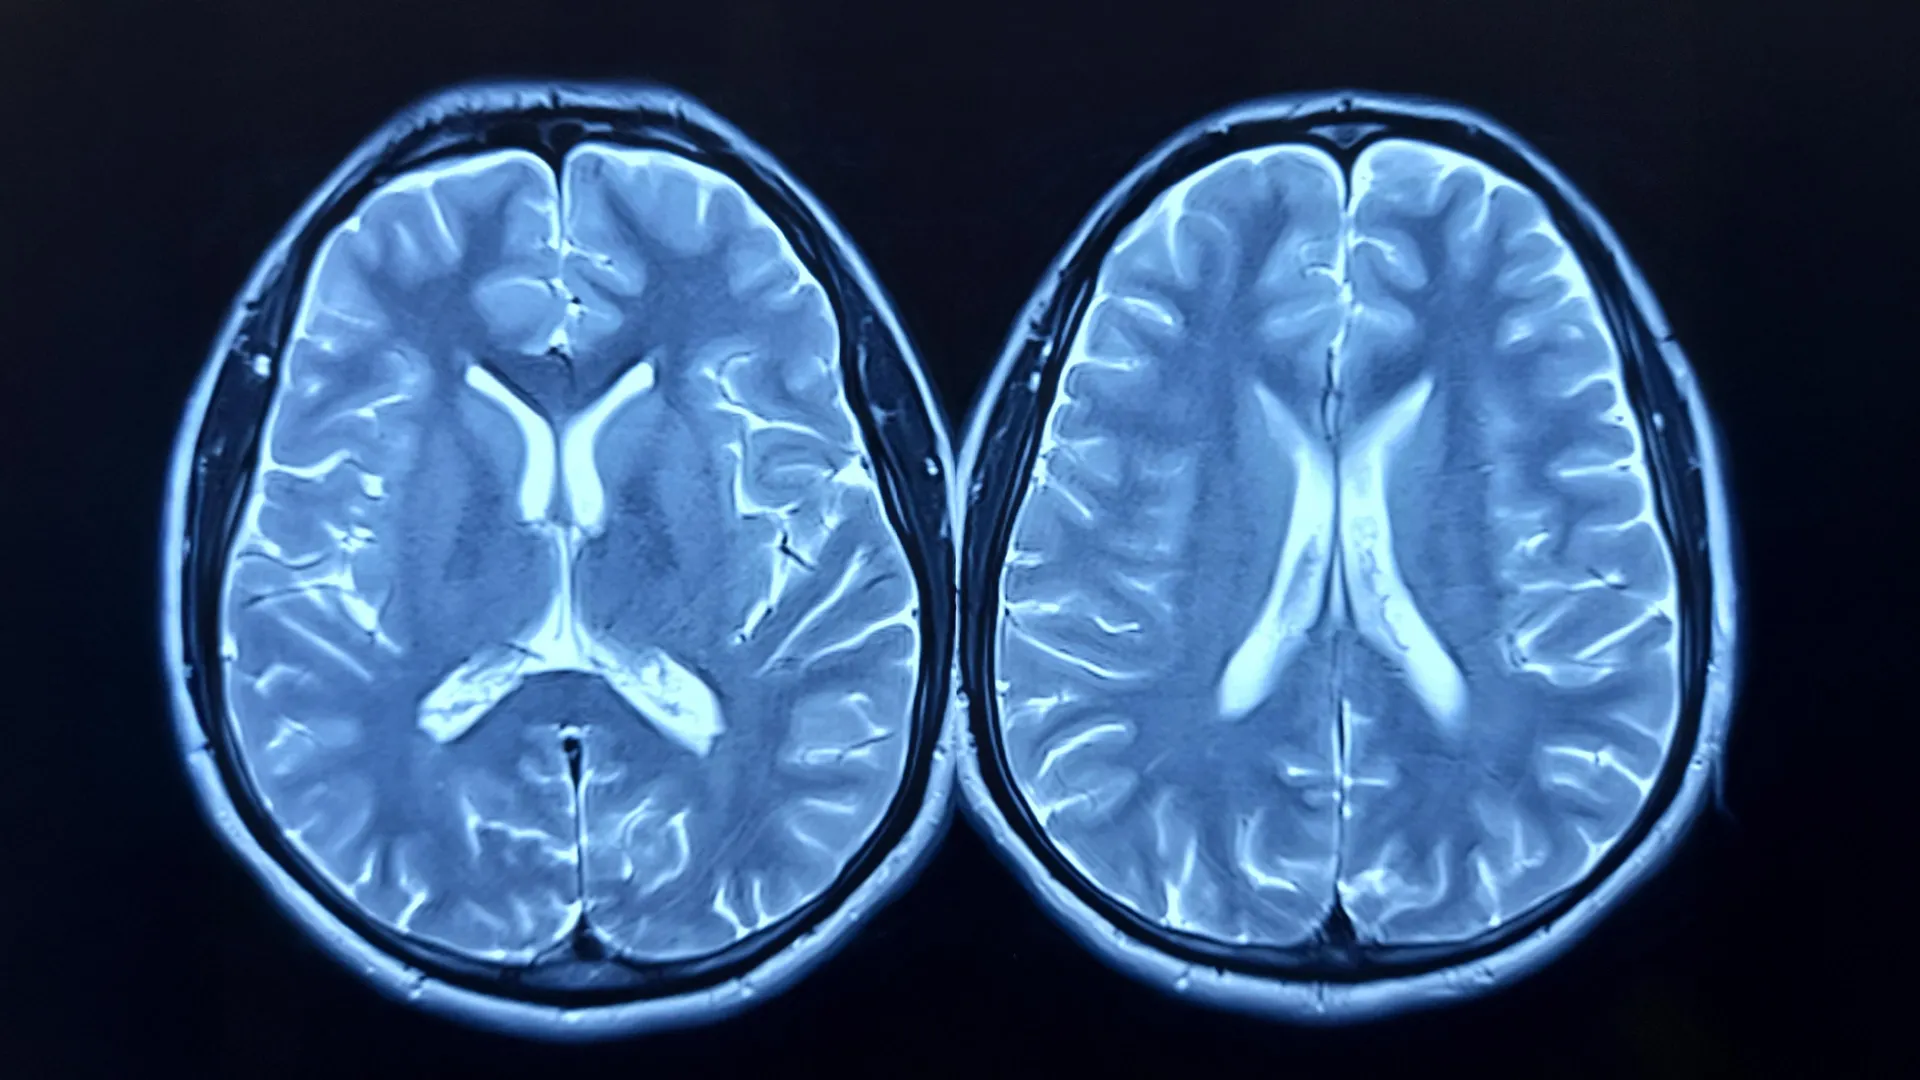

Medindo a idade do cérebro com ressonância magnética

Postado em Revista de Exercício e Ciências da SaúdeO estudo investigou se o exercício aeróbico regular poderia retardar ou até mesmo reverter o que os cientistas chamam de “idade cerebral”. A idade do cérebro é estimada por meio de ressonância magnética (MRI) e reflete a idade do cérebro em comparação com a idade real de uma pessoa. Uma maior diferença de idade prevista para o cérebro (brain-PAD) significa que o cérebro parece mais velho, e pesquisas anteriores associaram esta métrica a capacidades físicas e cognitivas mais fracas e a um maior risco de morte.

Os pesquisadores usaram exames de ressonância magnética para medir a estrutura cerebral e avaliaram a aptidão cardiorrespiratória por meio do consumo máximo de oxigênio (VO2pico) no início do estudo e 12 meses depois.